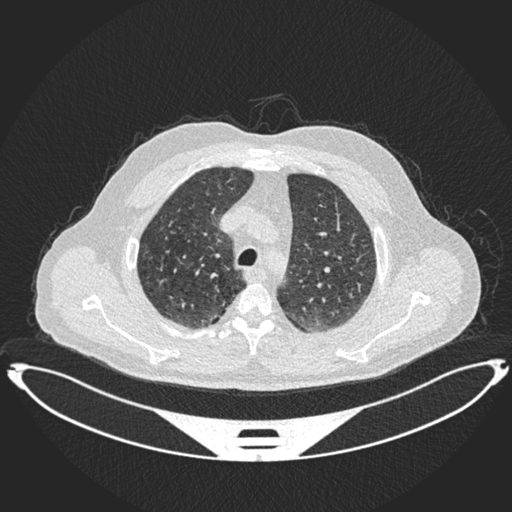

Analyzed Image

a.jpg

Uploaded: 2025-08-03 04:59:46Best Model Result

Normal

Confidence: 57.5%

Model: DenseNet121

Ensemble Prediction

Confidence: 39.5%

Average of all modelsModel Predictions Comparison

ResNet50

Malignant

32.1%

34.5%

33.3%

ConfidenceDenseNet121

31.6%

10.8%

57.5%

ConfidenceEnhancedCNN

19.7%

52.6%

27.7%